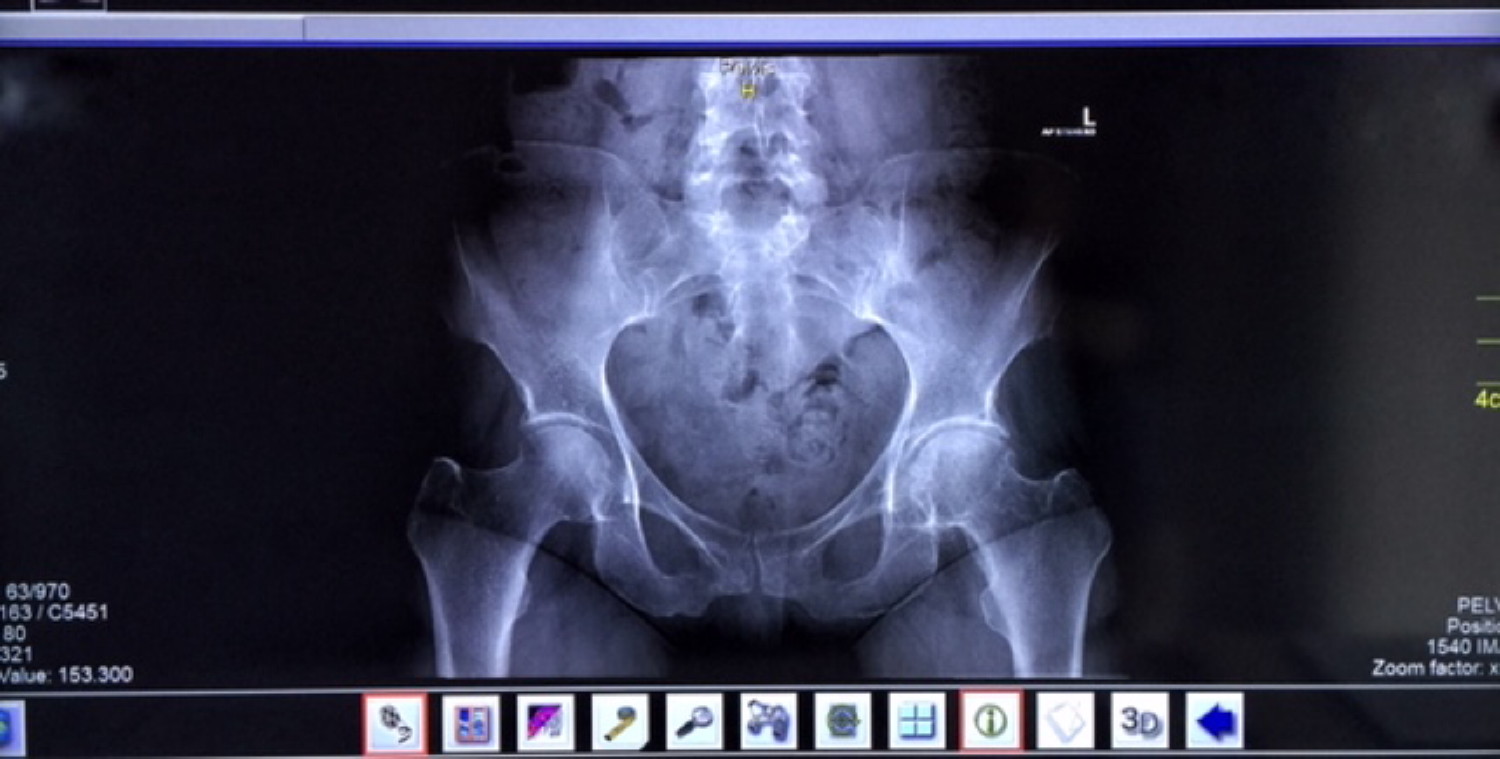

• Blockierte Rippengelenke, Schulter-Armschmerzen, gewisse Ellbogenschmerzen (z.B. Tennis- oder Golferellbogen), gewisse Formen von Hand- und Fingerbeschwerden (z.B. frühe Stadien von Karpaltunnelsyndrom). Hexenschuss, Ischias, chronische Kreuzschmerzen, gewisse Formen von Diskushernien und Skoliosen, Beckenverschiebungen, Steissbeinschmerzen, M. Scheuermann, M. Bechterew, Schwangerschaftsischias, funktionelle Hüft-, Knie- und Fussschmerzen.